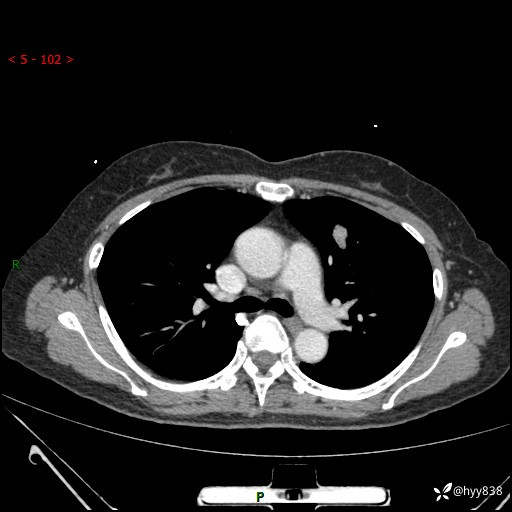

54岁/女,发现肺占位1天。观其形态和强化,术前我信心十足,术后我---结果公布~

【患者信息】:54岁/女

【主诉】:发现肺占位1天

【现病史及既往史】:患者2023.10.23体检发现肺占位:,2023.10.23当地区中心卫生院胸腹部CT:1.左肺上叶结节,考虑为占位可能;2.肝脏小囊肿灶;3.子宫左侧附件区畸胎瘤;无咳嗽咳痰,无恶心呕吐,无发热,无胸闷胸痛等不适;现患者为求进一步诊治来我院,门诊以“肺占位”收入我科。 患者自起病以来,精神饮食睡眠一般,大小便正常,体力体重无明显下降。

【检查】:胸部CT增强(外院平扫)